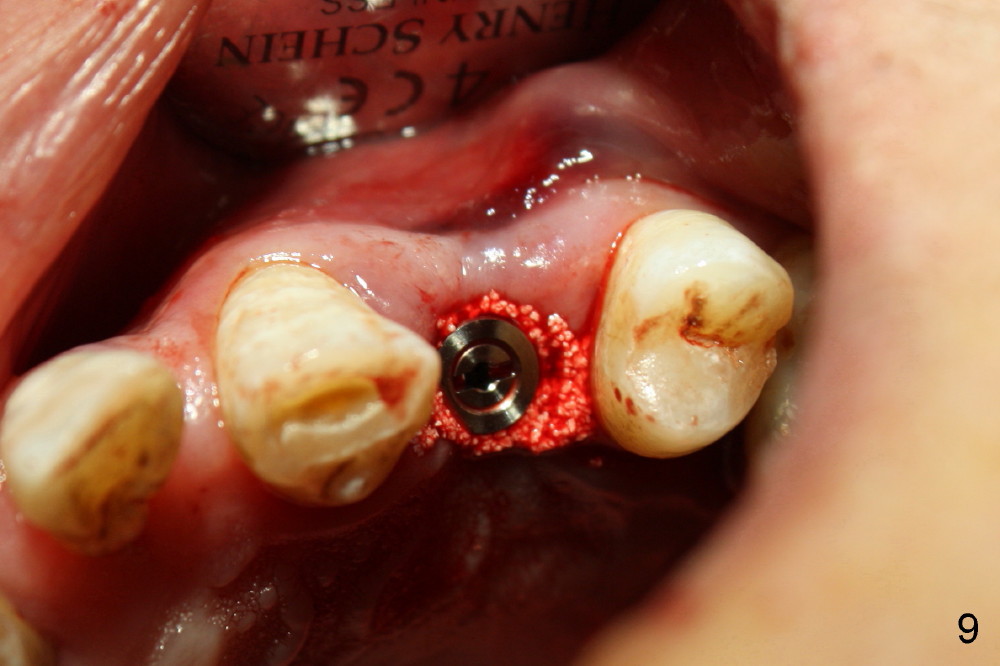

Dear Drs. Dunson and Borgner: Thank you for support. Fig.5 and 6 taken immediately prior to surgery show that the healing socket is elliptical (arrowhead). After D1 and D2 channel formers, D2 thin socket former is tapped in (Fig.7). The osteotomy needs to be redirected as shown by the black line. D2 implant is being inserted with Synthograft applied to the 1st two threads (Fig.8) and is in place (Fig.9,10). But the implant is not as stable as expected. There is a gap mesial to the implant (Fig.10 arrowhead), which is most likely created by re-directing the osteotomy with channel and socket formers.

Crestal bone grows 2 months (Fig.11), 3 months (Fig.12), 1 year (Fig.13) and 2 years 3 months (Fig.14) postop. When the periodontally-affected tooth is removed and bone graft is placed around the most coronal thread of the implant, bone will regrow as time passes by.